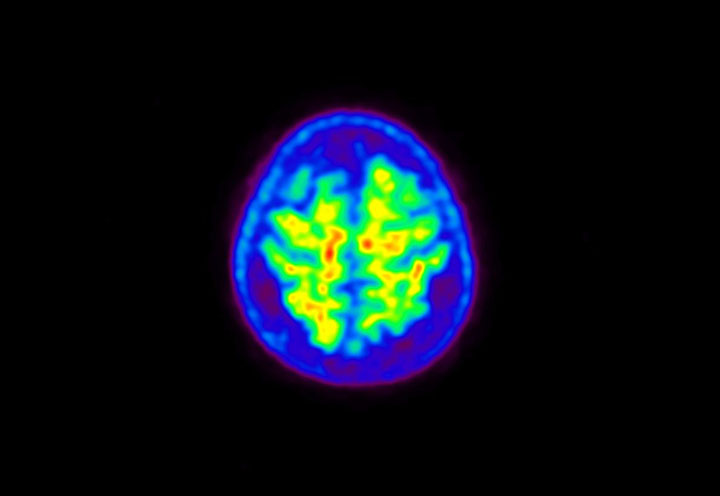

Head / Case5 : Amyloid

Courtesy : Kindai University Hospital

- Imaging protocol

- Injected dose: 4.27 MBq/kg, 18F-Flutemetamol

- Uptake time: 99 minutes

- Scan time: 20 minutes